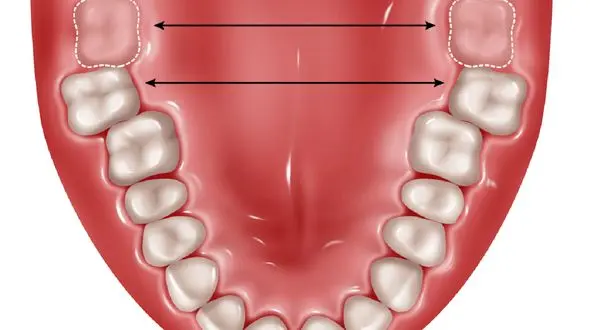

سلامت رکنا : دندان های عقل بالاترین شیوع نهفتگی را دارند و علت آن تغییر رژیم غذایی انسانها در طول سال هاست.